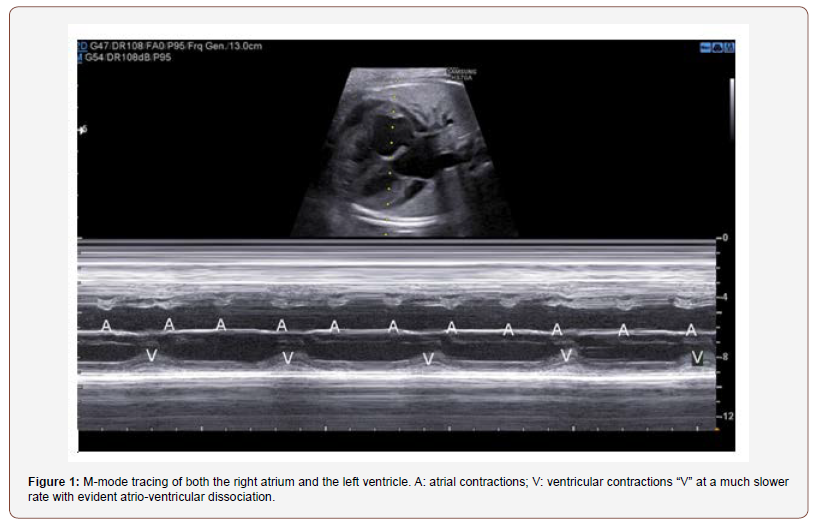

The obstetric ultrasound and echocardiography detected a structurally normal heart with a third-degree complete AV block with a complete dissociation between atrial and ventricular contractions (regular atrial rate of 130 bpm and a persistent ventricular rate of 55 bpm) (Figure 1, Video 1 and Video 2).

Video 1: M-mode with the M line passing through the right atrium and the left ventricle. It shows an atrial rate of 57 bpm and a ventricular rate of 123 bpm.

Video 2: B-Mode shows a complete dissociation between atrial and ventricular contractions.